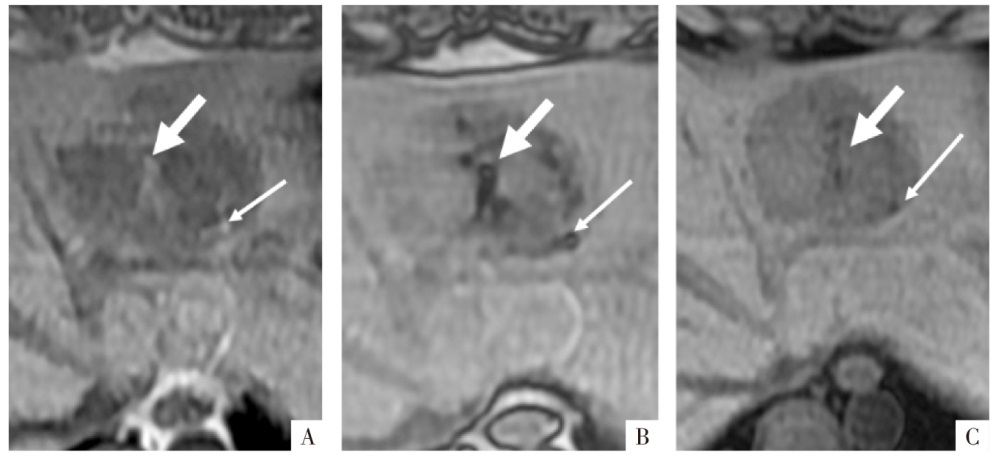

图4

病人女,42岁。手术病理证实为肝左外叶上皮样血管平滑肌脂肪瘤(细箭),内有直径约5 mm小块脂肪(粗箭)。A、B图分别为厚层同相位及反相位影像,层厚6 mm,矩阵256×180,同相位影像上含脂区域呈高信号(A),反相位影像上为含脂区域整体信号衰减(B),易误判为脂肪变性;C图为薄层高分辨力反相位影像,层厚3 mm,矩阵320×288,含脂区域中心仍呈高信号,周围可见勾边,为小脂肪块的典型表现。